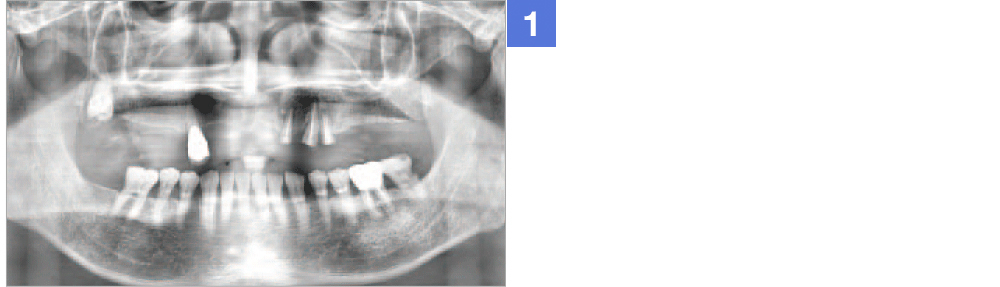

Through virtual operation procedure though 3D computer, DIO NAVI system decreases danger of implant surgery by checking patient's bone tissue and nerve position for planning the optimal surgery procedure and making customized surgical guide.

Through implant planning that considered occlusion and stress dispersion, DIO NAVI Digital Implant System increases the accuracy of the implant treatment and enabled 3D simulation that is used for patient counsel purposes.